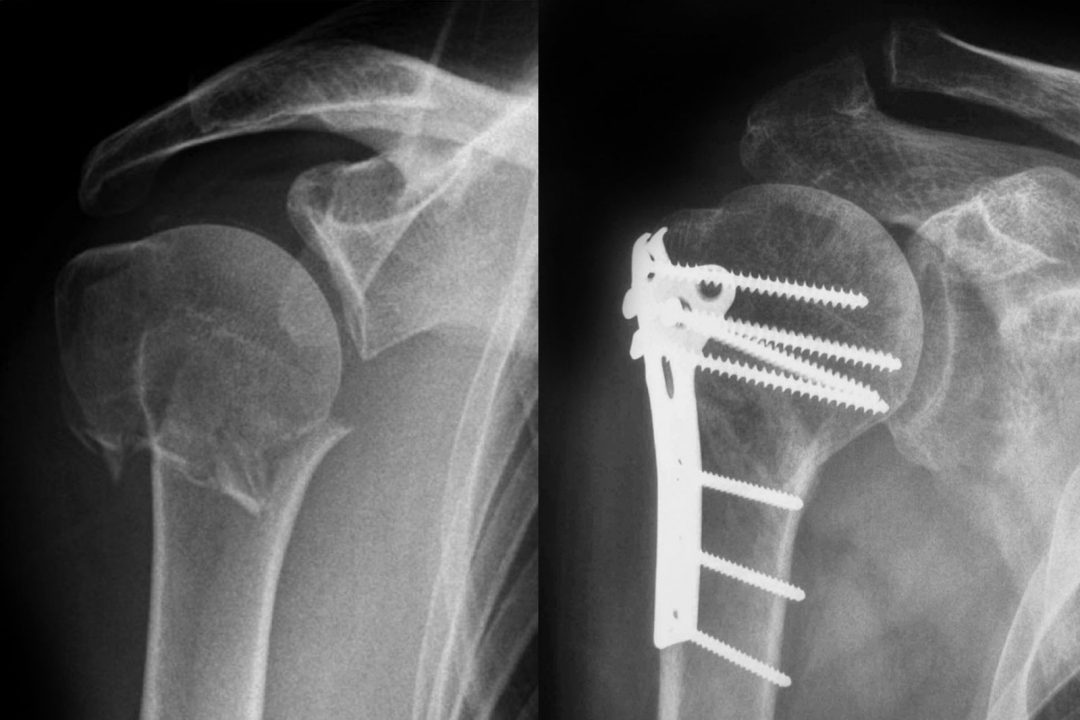

Kırık gelişmediği sürece osteoporozlu hastaların belirgin bir şikayeti olmamaktadır. Hayatları boyunca kadınların yarısı, erkeklerin 3’te 1’i kırık riski taşımaktadır. Osteoporoza bağlı olarak en sık el bileği, omurga ve kalça kırıkları görülmektedir. Bu kırıklardan en hayati öneme sahip olanı ise kalça kırıkları olmaktadır. Kalça kırıkları 75 yaş üzerinde ve kadınlarda erkeklerden iki kat fazla görülürken, bu kırık sonucunda damar tıkanıklığı ile akciğer embolisi gibi komplikasyonlar nedeniyle hastaların yüzde 15-20’si kaybedilmektedir.

Osteoporoz teşhisinde kemik yoğunluğu önemlidir ve bunu ölçmek için kemik dansitometresi denilen yöntem kullanılmaktadır. Dual Enerji X ışın Absorpsiyometri (DEXA) adı verilen ölçüm omurga ve kalça kemiğinden yapılabilmektedir. Ağrısız bir şekilde gerçekleşen ölçümün herhangi bir yan etkisi bulunmamaktadır. Bununla birlikte omurga kırıklarını görmek için sırt ve bel röntgen filmlerine de bakılabilmektedir.